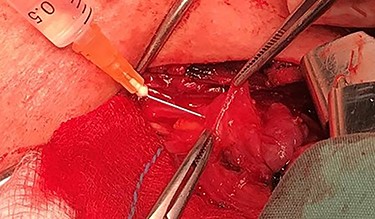

After a careful preparation of the anatomical structures of the neck and exposure of the thyroid gland, we proceeded to recognition of the parathyroid gland (Fig. 1). Then, glycerol solution was injected with a syringe of 2.5 ml and a needle of 26 gauges, to the loose connective tissue between the thyroid gland capsule and the parathyroid gland (Fig. 2). The amount that was administered was such as to produce the desired effect of tissue separation. By injecting the glycerol solution, the tissues swell, the size of the surgical field increases and the anatomical preparation of the parathyroid gland becomes simpler and with minimal parathyroid gland handling. A field like a glass is created, where the vasculature and the limits of the parathyroid gland are distinguished (Fig. 3). After that, a carefully dissection with a Mayo dissection scissor leaves the parathyroid gland intact. This technique is called TDSI.

Solution injection with a syringe of 2.5 ml and a needle of 26 gauges, to the loose connective tissue between the thyroid gland capsule and the parathyroid gland.